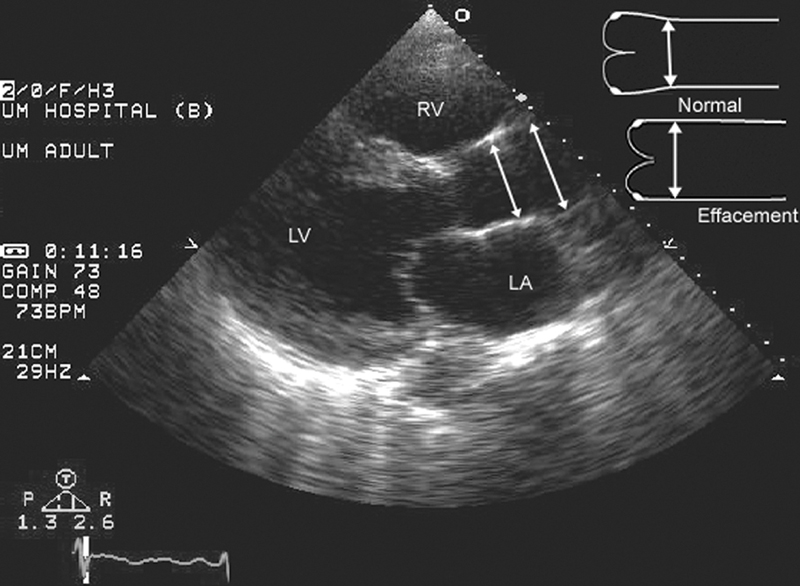

فحوصات تشخيصية لبعض امراض القلب والشرايين التاجية